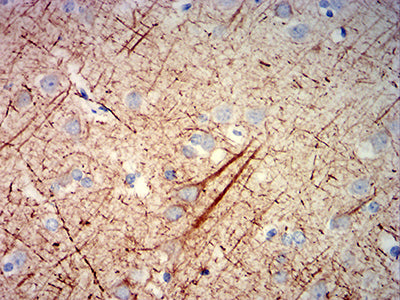

分类: 科研抗体货号: 31909别名: NFH; CMT2CC应用: IHC,FCM反应种属: Human